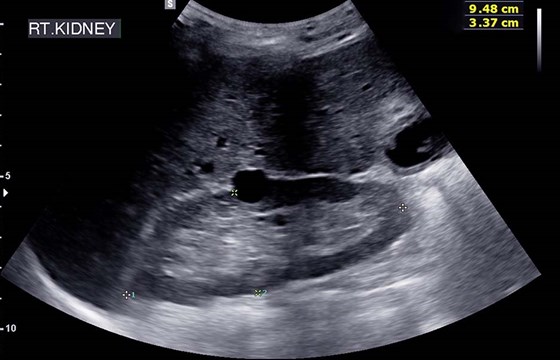

USG układu moczowego służy do oceny stanu nerek, pęcherza moczowego oraz moczowodów, a w przypadku mężczyzn – gruczołu krokowego. Badanie pozwala wykryć:

- zmiany ogniskowe, do których należą torbiele i guzy,

- kamicę nerkową,

- wodonercze,

- zwężenie tętnicy nerkowej,

- zmianę rozmiaru moczowodu,

- zastój moczu.